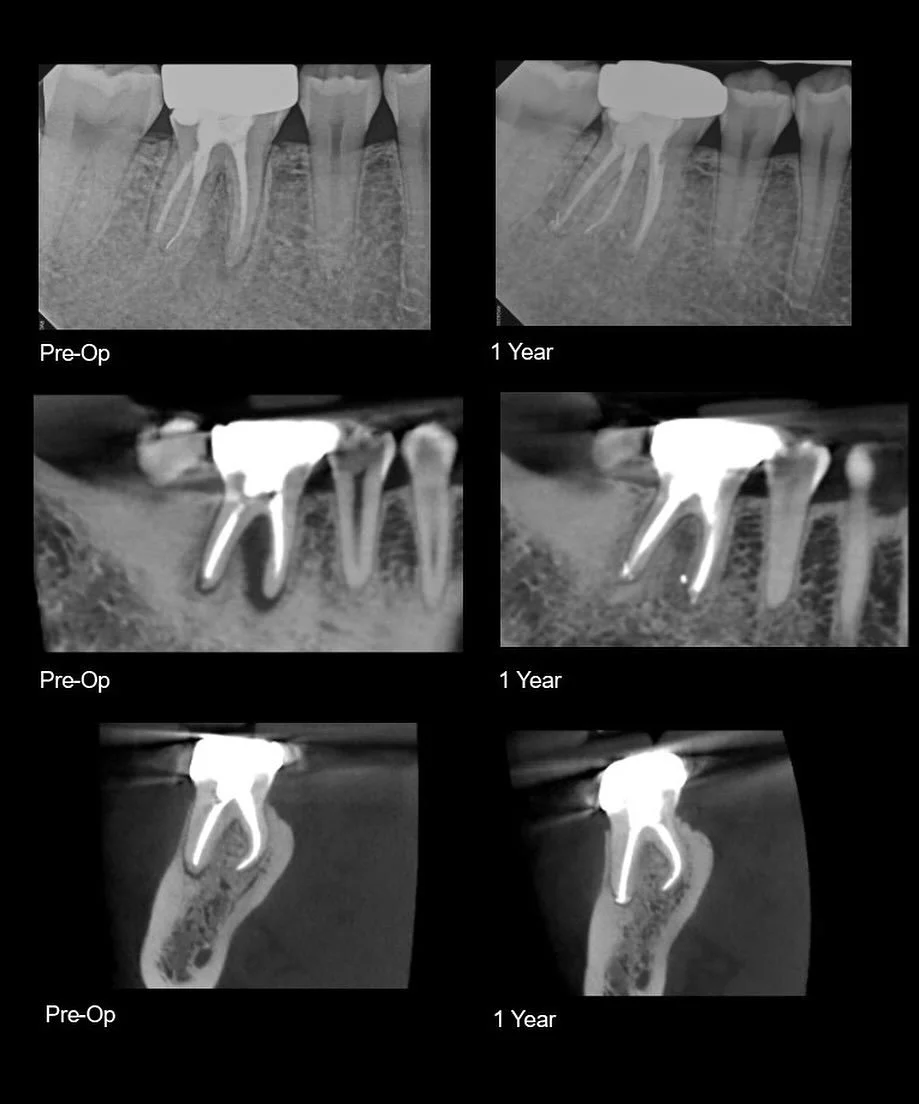

I am a board-certified endodontist with advanced specialty training and an academic interest in diagnostic reasoning, retreatment, and microsurgical endodontics. My work emphasizes CBCT-guided decision-making, interdisciplinary collaboration, and evidence-based care in complex clinical scenarios.

Board certification in endodontics represents an advanced level of professional achievement beyond specialty training. It is a voluntary, multi-year process that requires successful completion of a comprehensive written examination and rigorous peer review of complex clinical cases, evaluating diagnostic judgment, technical execution, and long-term outcomes. Less than 25% of practicing endodontists achieve board certification, reflecting a commitment to clinical excellence, continual self-assessment, and the highest standards of the specialty.